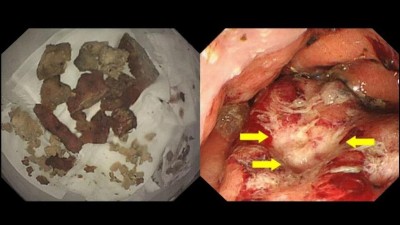

Endoscopic removal of an impacted sponge

Five-pronged grasping forceps were required to remove a sponge impacted in the esophagus of an 81-year-old woman with dementia. An esophageal ulcer found during follow-up endoscopy was treated with a PPI.

Boy looking unhappy/© airdone / iStock / Getty Images Plus (symbolic image with model), Older man trying to sleep/© amenic181 / Getty Images / iStock (symbolic image with model), Brain inside a medicine capsule/© Jorg Greuel / Getty Images, Speech therapy/© wanderluster / Getty Images (symbolic image with models), Ocular examination of patient with corneal melting/© 2025, Rawan Hosny et al, BMC Ophthalmol, Human brain illustration/© (M) CHRISTOPH BURGSTEDT / SCIENCE PHOTO LIBRARY / Getty Images, Head with puzzle pieces/© Berit Kessler / Generated with AI / stock.adobe.com, Woman at a medical consultation/© Antonio_Diaz / iStock / Getty Images Plus (symbolic image with models), Older Black man exercising at the seaside/© JLco - Julia Amaral / Getty Images / iStock (symbolic image with model), Neuropathological findings in iatrogenic cerebral amyloid angiopathy/© 2025, Ana Sofia Costa et al, Neurol Res Pract, A fragment of sponge extracted from the esophagus and an endoscopic view of ulcer formation within the hernial sac/© (M) 2025, Keisuke Ojiro et al, Clin J Gastroenterol, under exclusive licence to the Japanese Society of Gastroenterology, Medicine Matters Podcast promo image/© Springer Medizin GmbH, Navigating neuroimaging in Alzheimer’s care: Practical applications and strategies for integration/© Springer Healthcare IME, Alzheimer’s disease in the biomarker era: preparing the multidisciplinary care team/© Springer Healthcare IME, EAMN Logo/© Springer Healthcare IME